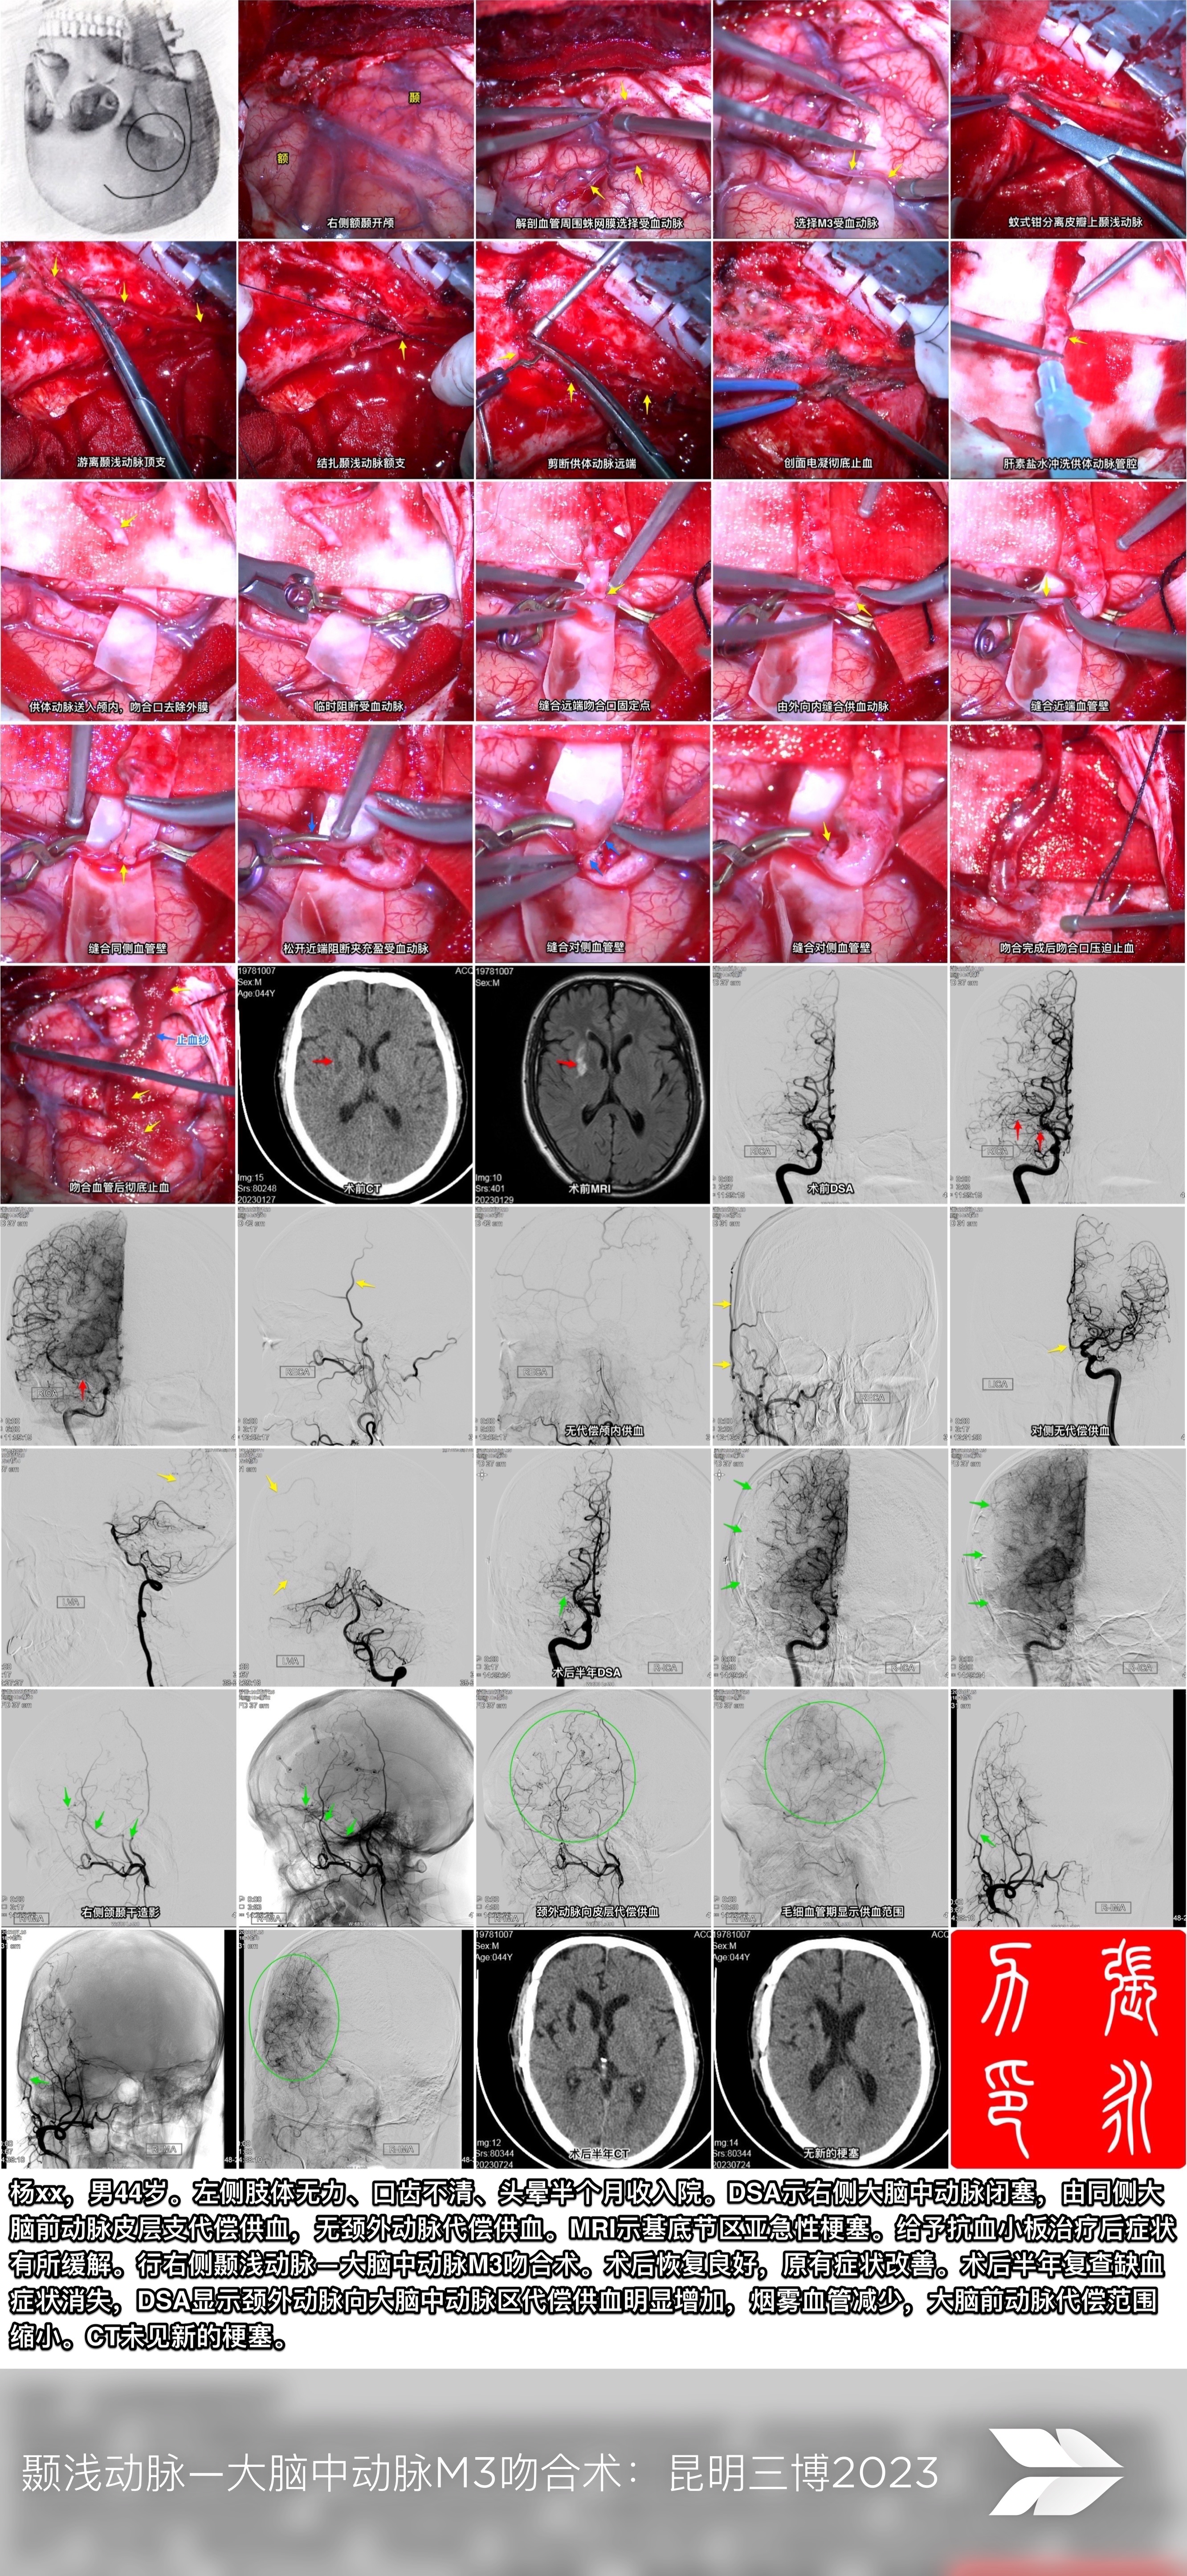

昆明三博2023:颞浅动脉一大脑中动脉M3吻合术